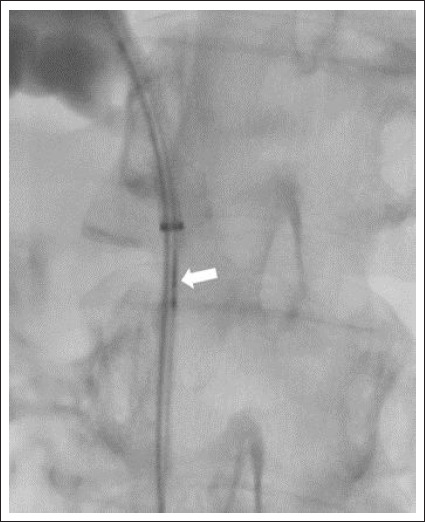

Materials and methods: This retrospective, single-center study was conducted between January 2022 and April 2023, involving a total of 16 patients. Of the patients, 10 were male (62.5%), and 6 were female (37.5%). The average age of the patients was 68.1±8. All patients underwent the procedure using an endobiliary biopsy brush under ultrasound and fluoroscopic guidance.

Results: Technical success was achieved in all patients (100%). Cell detection was not observed in biopsy samples from 2 patients (12.5%), resulting in a diagnostic success rate of 87.5%. Access was made to the right biliary system in 14 patients (87.5%) and to the left biliary system in 2 patients (12.5%). Biopsy locations included the common bile duct in 12 patients (75%), hepatic hilum in 2 patients (12.5%), and bilioenteric anastomosis line in 2 patients (12.5%). The mean fluoroscopy time was 16.2±7.1 minutes. The average radiation dose was 660±370 mSv. Pathological diagnosis revealed malignancy in 8 patients (50%) and benign findings in 6 patients (37.5%). Liver abscess requiring drainage developed in 2 patients (12.5%).

Abstract Image